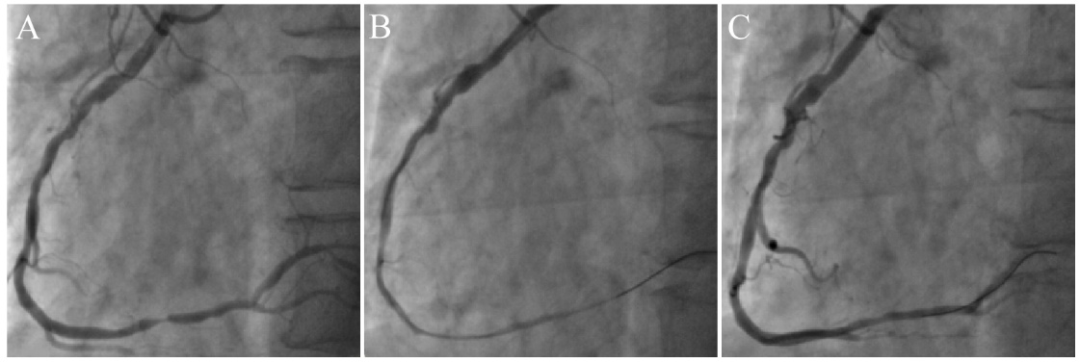

图11 球囊诱发冠脉痉挛。

右冠弥漫性病变,远段最重狭窄95%(A),药物球囊处理后弥漫性变细(B),注射硝酸甘油后缓解(C)。

图12 导管深插诱发顽固性痉挛。

JR4造影导管深插至右冠(A),退至开口造影提示近段严重狭窄(B),冠脉内注射硝酸甘油200μg×3次只有部分缓解(C),继续推注200μg×2次后基本缓解(D)。说明部分患者强刺激后痉挛比较持久。该病人并无血管痉挛的临床表现,术后不需要抗痉挛治疗。